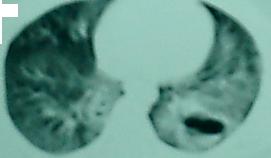

病人,男性,17岁,因车祸被120送到医院,做双髋ct示右髋臼粉碎性骨折,另做胸部ct偶然发现两肺多发空洞,向病人询问病史,既往无咳嗽/咳痰及胸痛.亦无午后低热及盗汗.后住院期间查血常规示白细胞和中性粒细胞比例增高

左下肺发育不良伴两肺多发囊肿,瞎猜的,哈

双下肺囊肿合并感染或特殊致病菌感染。但也不排除发育不良。